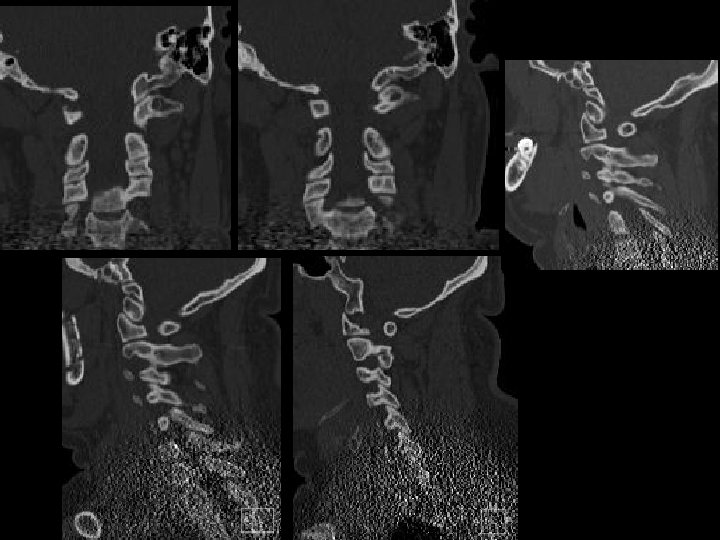

Son fracturas/ espondilosisis? ? Busquemos falsos !!

Diagnósticos diferenciales? ? ? Núcleos de osificación 2 darios Hendiduras/grietas (Clefts) Núcleos de Schmorl Limbus vertebra Improntas vasculares Malformaciones Oseas Artificios

Ejemplos! Arco anterior bipartito Arco posterior fusión incompleta Fx vs no fx !!

Fracturas vs nucleos de osificacion secundarios Ver: bordes irregulares vs bordes esclerosos y lisos!!!

Sitios de hendiduras!